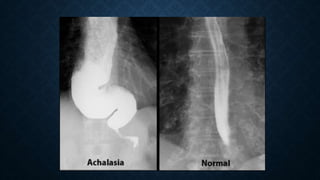

This document provides an overview of x-rays for medical students, covering topics such as ensuring x-rays are well-aligned, exposure levels, common artifacts and anatomical features, abdominal x-ray positions and views, and specialized x-rays including barium swallows, enemas, and tests to examine the esophagus, small bowel, biliary tree, and kidneys.